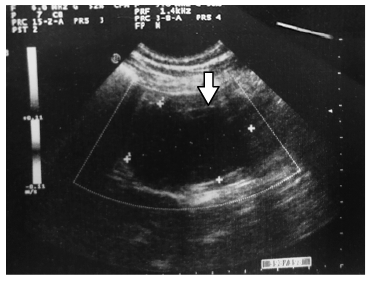

Se le realizaron exámenes de laboratorio que dieron como resultado una alcalosis metabólica, un aumento de los glóbulos blancos (90% polimorfonucleares), amilasa elevada (236 UI/L) y lipasa también alta (140 UI/L). La ecografía abdominal mostró una imagen ovoidea bien delimitada, hipoecoica de 50 x 26 x 26 mm de tamaño, con una ecotextura heterogénea y sin vascularización en la exploración Doppler, compatible con un hematoma de la segunda porción del duodeno (Figura 1). Esto se confirmó mediante una tomografía axial computarizada con y sin contraste intravenoso, estableciendo la ubicación no solo en la segunda, sino también en la tercera porción del duodeno y de un diámetro de 50 mm (Figura 2).